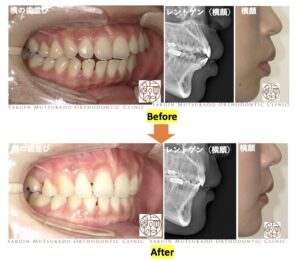

治療前後の写真です↓↓

横顔の変化の写真です↓↓

上下の前歯を後方に下げたことで上下の口唇の突出感は改善されました。